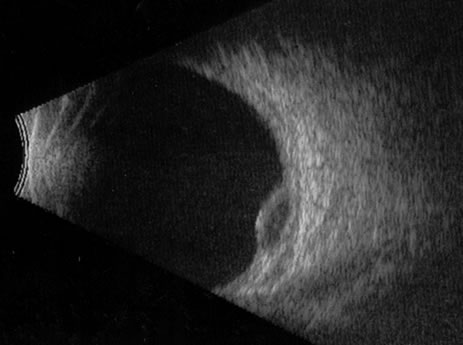

Necrotic melanomas account for approximately 5% of uveal melanomas; in the majority of cases, there is intraocular inflammation accompanying the cataract.7–9Figures 1 and 2 demonstrate a typical case. The patient had a long history of unilateral decreased vision. The eye had become painful 1 month before admission, and he was referred for evaluation of uveitis. Clinically, there was a dense, unilateral cataract with significant intraocular inflammation, which was manifested as a ciliary flush with 2+ cells and flare. Media opacity obscured all fundus detail. An immersion B-scan demonstrated a large intraocular tumor that was most consistent with a uveal melanoma. The eye was removed, and the diagnosis was confirmed histologically.10

|